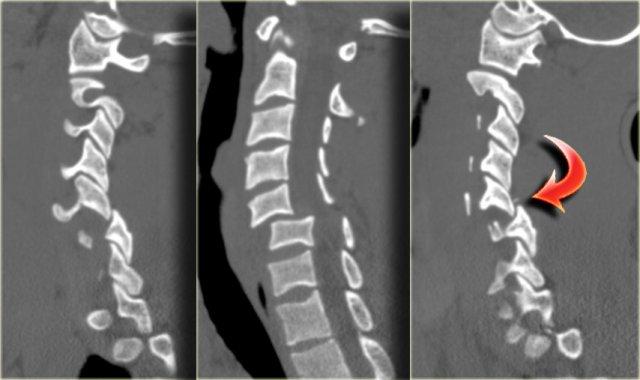

Trật khớp mặt hai bên (Bilateral Interfacetal Dislocation)

Trật khớp mặt hai bên (BID) là hậu quả của tăng gấp cực độ.

Có sự trật khớp ra trước của các khối khớp kèm phá vỡ phức hợp dây chằng phía sau, dây chằng dọc sau, đĩa đệm và thường cả dây chằng dọc trước.

Khi trật khớp hoàn toàn, đốt sống bị trật di lệch ra trước một nửa đường kính trước-sau của thân đốt sống.

Do tổn thương mô mềm lan rộng và trật khớp mặt, BID là chấn thương không vững và có tỷ lệ cao tổn thương tủy sống kèm theo.

Các dấu hiệu bao gồm:

- Trật khớp mặt hai bên.

Di lệch ra trước 50% tại C5-C6 do trật khớp.

Trong trật khớp một bên, mức độ di lệch ra trước thường chỉ là 25%. - Khoang gian gai giữa C5 và C6 rộng ra do đứt dây chằng.

- Rách khoang đĩa đệm.

Bên trái là hình CT của cùng bệnh nhân, xác nhận trật khớp hai bên.

Gần một trong các khớp mặt có một mảnh xương nhỏ, nhưng không có gãy xương lớn, vì vậy về cơ bản đây chỉ là chấn thương mô mềm tăng gấp.